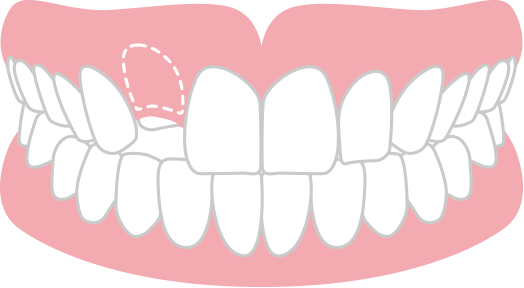

永久歯が生えてこない 埋伏歯

何らかの原因で永久歯の生え進む方向が悪くなり、生えてこられない状態。歯が完全に粘膜の下にある場合を完全埋伏、歯の一部でもお口の中に出ている場合を不完全埋伏といいます。

長年放置すると、隣の永久歯の根を吸収するため、早期に治療する必要があります。3歯以上埋伏歯がある場合は、矯正歯科治療が保険適用になります。